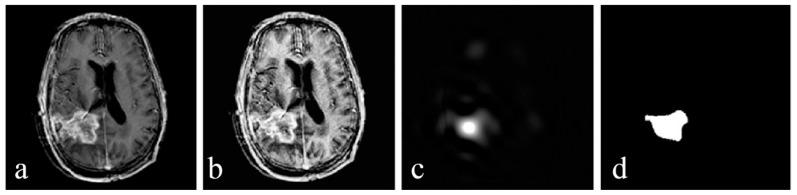

For the fusion of MRI gray scale images and PET color images, we used lesion region extracting based on the digital Curvelet transform (DCT) method. As curvelet transform has a better performance in detecting the edges, regions in each image are perfectly segmented. Curvelet decomposes each image into several low- and high-frequency sub-bands. Then, the entropy of each sub-band is calculated. By comparing the entropies and coefficients of the extracted regions, the best coefficients for the fused image are chosen. The fused image is obtained via inverse Curvelet transform. In order to assess the performance, the proposed method was compared with different fusion algorithms, both visually and statistically.

The analysis of the results showed that our proposed algorithm has high spectral and spatial resolution. According to the results of the quantitative fusion metrics, this method achieves an entropy value of 6.23, an MI of 1.88, and an SSIM of 0.6779. Comparison of these experiments with experiments of four other common fusion algorithms showed that our method is effective.

对于MRI灰度图像与PET彩色图像的融合,我们采用基于数字曲波变换(DCT)方法的病变区域提取。由于曲波变换在检测边缘方面具有更好的性能,每个图像中的区域都能被完美分割。曲波将每个图像分解为几个低频和高频子带。然后,计算每个子带的熵。通过比较提取区域的熵和系数,选择融合图像的最佳系数。通过逆曲波变换获得融合图像。为了评估性能,将所提出的方法与不同的融合算法在视觉和统计方面进行比较。

结果分析表明,我们提出的算法具有高光谱和空间分辨率。根据定量融合指标的结果,该方法的熵值为6.23,互信息(MI)为1.88,结构相似性指数测量值(SSIM)为0.6779。将这些实验与其他四种常见融合算法的实验进行比较表明,我们的方法是有效的。